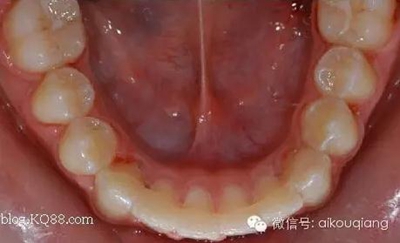

1、如果透明壓膜正畸保持器的保持范圍從7做到7,這時候由于保持器PVC片厚度的墊高作用,而產(chǎn)生的剪刀效應(yīng)使病人戴上保持器后前牙基本就成開合狀態(tài),這樣病人白天戴做后感覺很不舒服,因為不能很好的回復(fù)到息止合位,而夜晚戴上也會因為前牙的開合形成口呼吸習(xí)慣。除此之外!其本身還有一個缺點就是因為有一部分病人帶環(huán)是只做在6上,而7并沒有納入矯正系統(tǒng),所以7有的時候位置不是很理想的狀態(tài),大部分病人在沒有干擾因素的前提下,7大部分回回復(fù)到基本正常的位置,但現(xiàn)在由于被透明正畸保持器保持住了而無法自行調(diào)整!此也為其一大缺點!

2、如果您未了為了克服第一條所說的缺點,而把透明正畸保持器只做到6--6,但這時同樣又帶來了另一個缺點,就是病人在開始的半年內(nèi)是不能日夜都戴的,否則由于6-----6牙被透明正畸保持器墊高,而上下7被日夜懸空,對處于生長發(fā)育階段的病人,且非常認真按醫(yī)生的醫(yī)囑戴的病人,其上下7非常有可能升長,當(dāng)幾個月后病人來做例行的檢查復(fù)診,你就會很大的驚訝,發(fā)現(xiàn)自己辛苦矯正好的病例,變成了一個只有7--7接觸的開合病例,這時候你會很頭大!而如果為了克服這一致命缺陷,只好叫病人只在病人夜間戴用透明壓膜保持器,但這又不符合保持器開始半年內(nèi)必須日夜戴用的原則!取不到理想的保持效果!